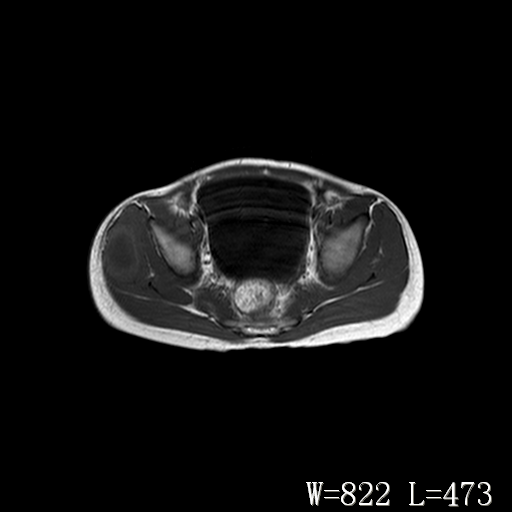

男,6岁,发现右臀部肿块10余天。

右侧臀部较大囊性肿块,长t1、长t2信号改变,周围组织信号正常,不知有否局部注射史?如果有,则支持脓肿,否则要考虑血管瘤可能。